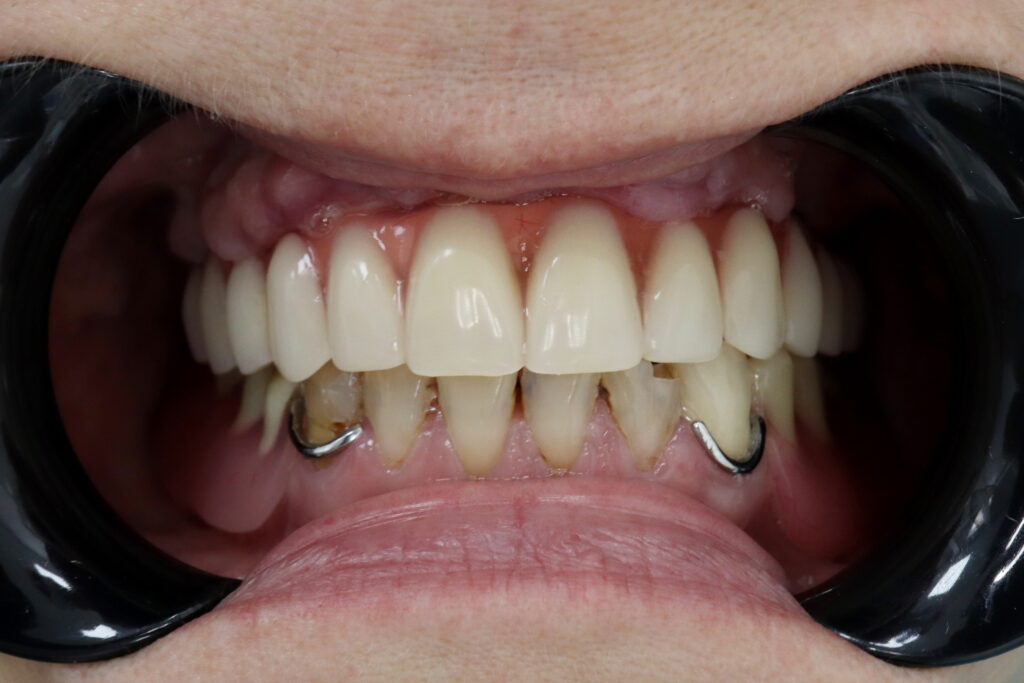

Ситуация до лечения

Диагноз: Полная адентия верхней челюсти и частичная вторичная адентия нижней челюсти.

пациент до имплантации